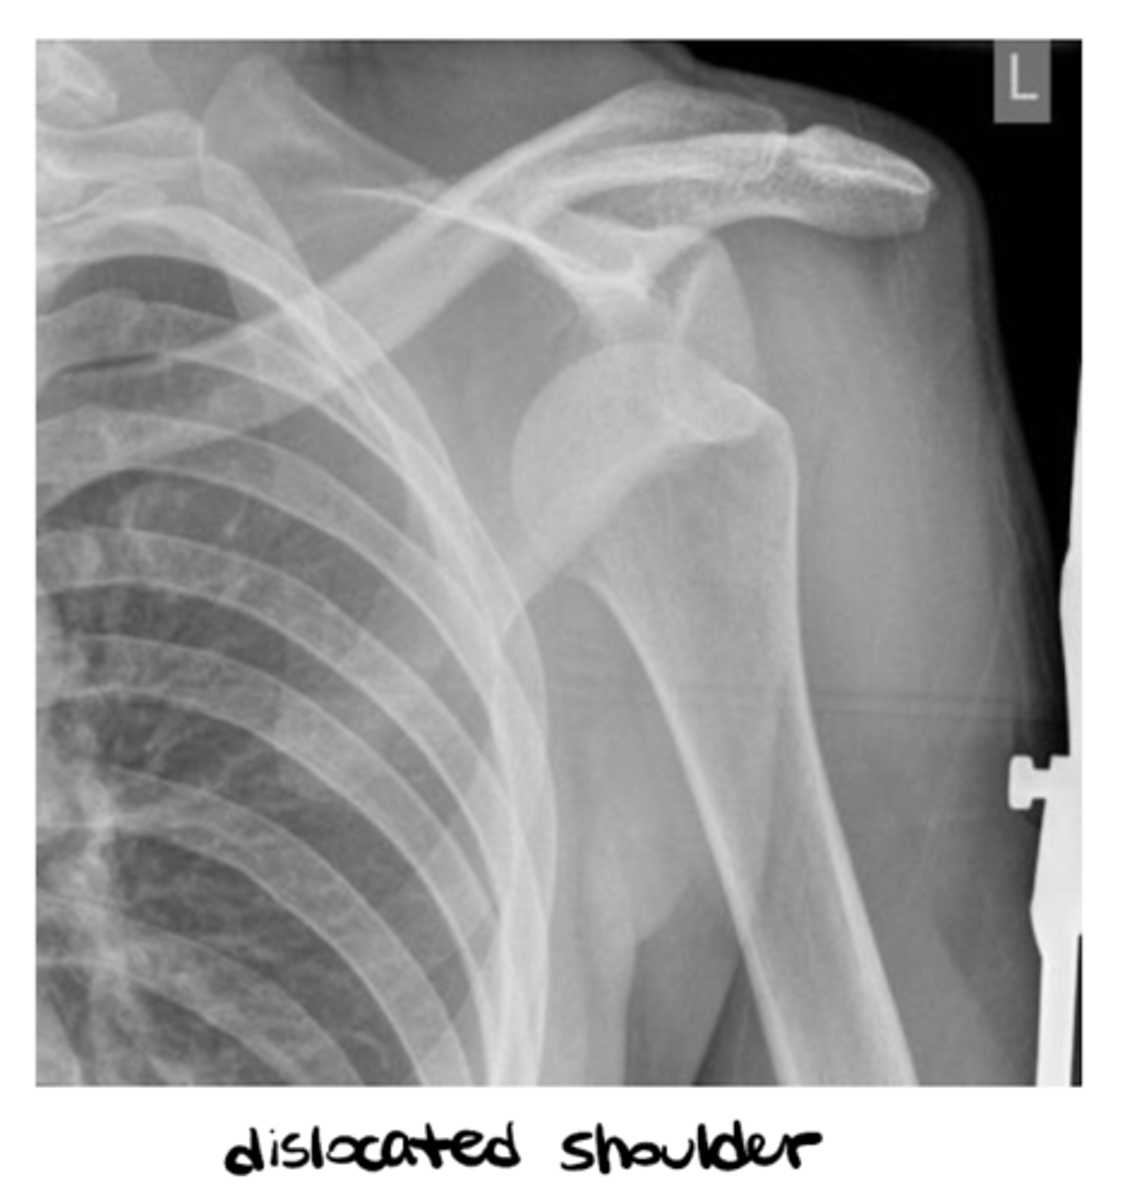

- Dislocation

- Subluxation

1. "Significant" trauma (severity, suspected fracture, dislocation, radiating pain)